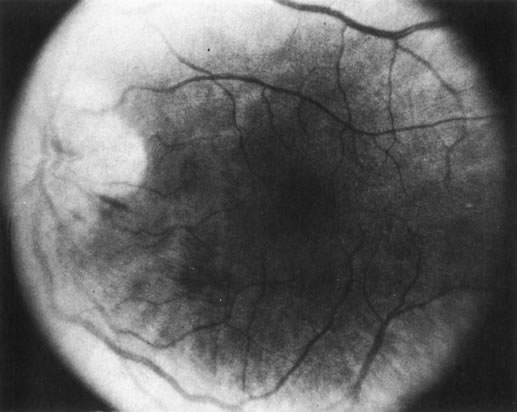

3. Diffuse retinoblastoma, which accounts for less than 2% of cases, often does not produce a discrete tumor (Fig. 26). The diffuse cases I have managed have had atypical retinal detachments without clinical, CT, or ultrasonographic evidence of a calcified tumor mass. Diagnosis has been established with an intraocular FNAB.55

Fig. 26. Diffuse retinoblastoma without an obvious tumor mass.